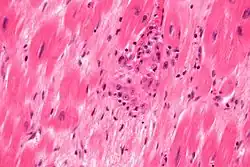

In pathology, Aschoff cells (or Aschoff giant cells) are cells associated with rheumatic heart disease. They are found in Aschoff bodies surrounding centres of fibrinoid necrosis.

In comparison with Anitschkow cells their cytoplasm is more basophilic and can contain up to four nuclei.[1]

Aschoff believed that Aschoff giant cells were some type of connective or endothelial tissue.[2] Today Aschoff cells are considered to be derived from cardiac myocytes rather than connective tissue cells.[1]